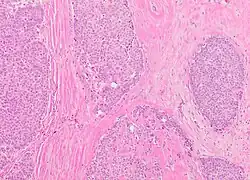

The microscopic histopathology of typical PDCIS lesions (refer to adjacent high-power photomicrograph) prepared with a hematoxylin and eosin stain consists of mammary ducts that have papillary fronds (i.e. thin, finger-like or leaf-like structures) lined with one or several layers of neoplastic, columnar-shaped epithelial cells (i.e. tall, narrow cells with their nuclei close to the site of their ductal attachment).[4] The fronds have branching fibrovascular cores. Epithelial cells lining the fronds' inner surfaces commonly form solid, cribriform (i.e. large nests of cells perforated by many rounded, variably sized spaces), or micro-papillary patterns. There may be a second population of epithelial cells lining the papillae that have abundant clear cytoplasm in addition to the usual neoplastic epithelial cells which line the papillae. These cells, which are not myoepithelial cells, have been termed globoid cells.[7] They have eosinophilic cytoplasm (i.e. pink or red cytoplasm due to its uptake of eosin stain).[6] PDCIS tumors with these cells have been termed dimorphic variants of PDCIS.[3] Myoepithelial cells are typically present at the periphery of the fronds but absent within the involved ducts.[4][7] The presence of a fibrous capsule and/or absence of peripherally located myoepithelial cells are strong indicators that the tumor is an ESP rather than a PDCIS.[3] PDCIS tissues may also contain areas of "Comedo-type necrosis", i.e. areas where dead cells have accumulated.[6]